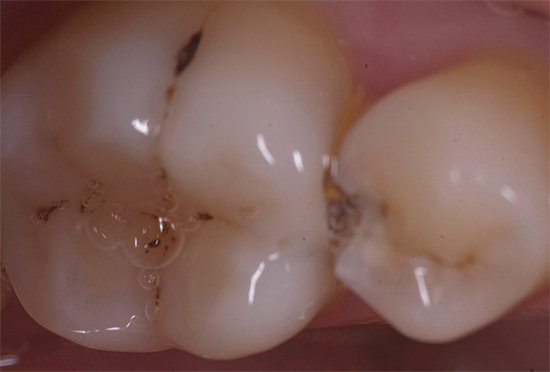

Foto di carie profonde sul dente anteriore: